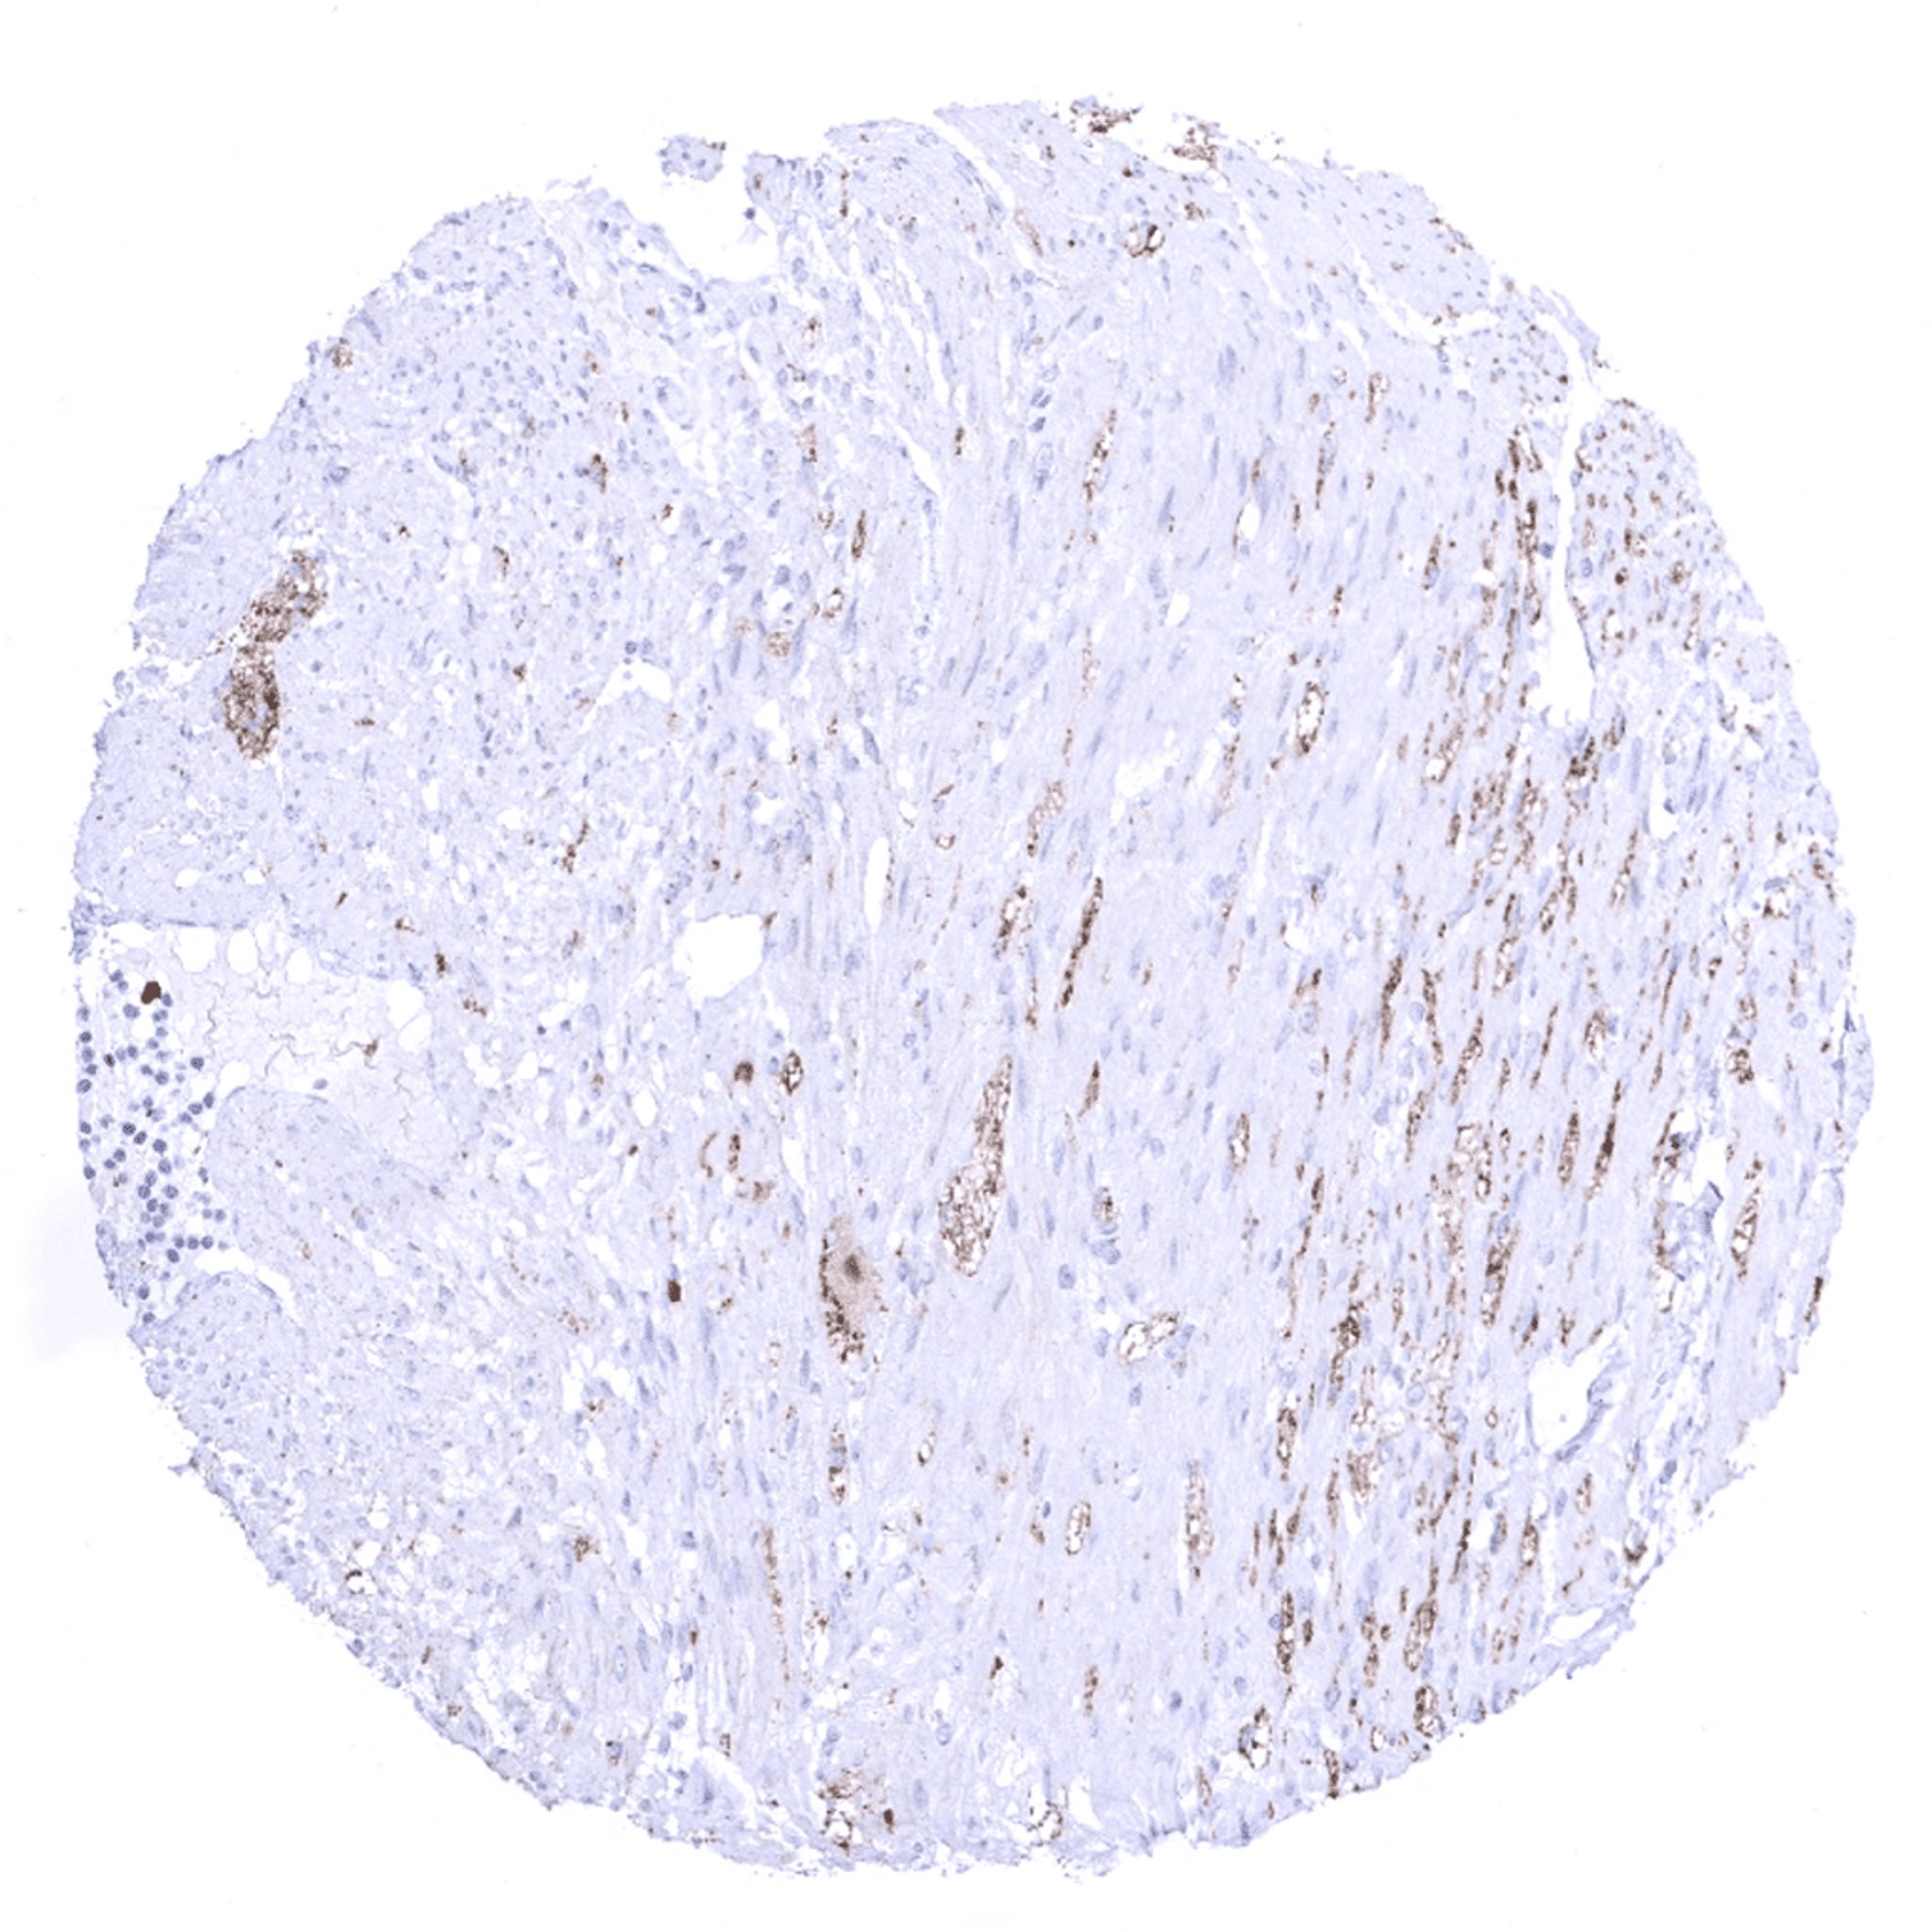

Uterus, myometrium